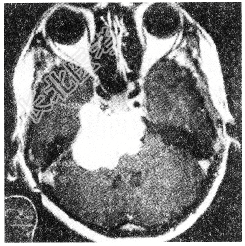

- 多项选择题下列哪些符合脑膜瘤(如图所示)表现

A、脑膜瘤起源于蛛网膜细胞丛,与蛛网膜颗粒关系密切

B、脑膜瘤起病慢、病程长,可达数年之久

C、初期症状及体征不明显,以后逐渐出现颅内高压症部定位症状及体征

D、颅内高压症的出现通常提示瘤体已较大或肿块阻塞脊液通道

E、局部定位征象因肿瘤所在部位而异